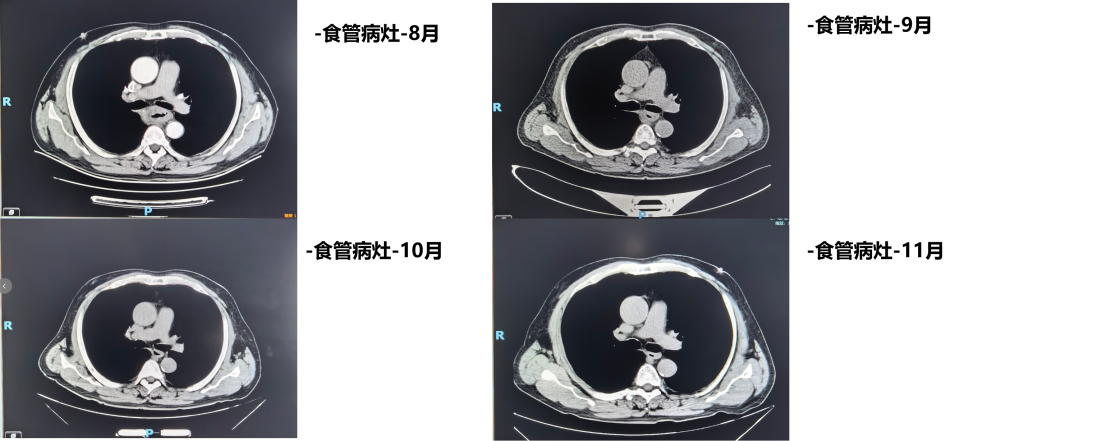

1周期后(2025年9月)复查CT:食管病变、纵隔淋巴结较前减小,双肺转移结节较前部分减小。1周期即显现疗效。

4周期后(2025年11月)复查CT:与2025-10-17日图像对比,食管癌治疗后改变,同前相仿;纵隔淋巴结治疗后改变,较前减小;双肺多发小结节,考虑转移瘤治疗后改变,部分较前略减小。

疗效评估:达到部分缓解(PR)

本例患者PD-L1 CPS评分为3分,属于CheckMate 648研究中获益更为显著的PD-L1阳性人群。经过4个周期纳武利尤单抗联合化疗后,影像学复查显示原发灶及所有转移病灶均明显缩小,疗效评估达PR,与研究中PD-L1阳性患者高达53%的ORR相符。